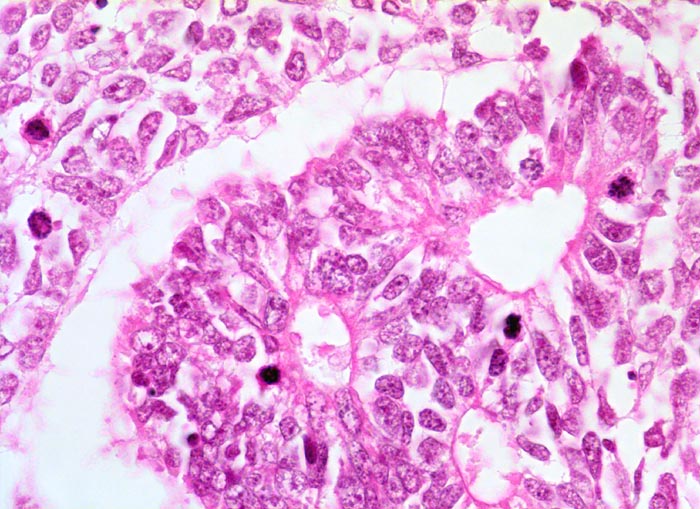

PathoPic – image database / PathoPic ID 5183 - Wilms-Tumor

Wilms-Tumor

maligner Tumor

Niere

Tubuli ausgekleidet von stark basophilem Epithel mit grossen Kernen. Kerne mit kleinen Nukleolen und grobem Chromatin. Daneben solide Blastemkomponente mit ähnlicher Zytomorphologie. In beiden Komponenten finden sich Mitosen.

Graubrauner scharf begrenzter weicher Tumor mit fokalen Nekrosen und Einblutungen.

Palpabler Tumor im linken Hemiabdomen. Makrohämaturieepisode.

Histologie

500